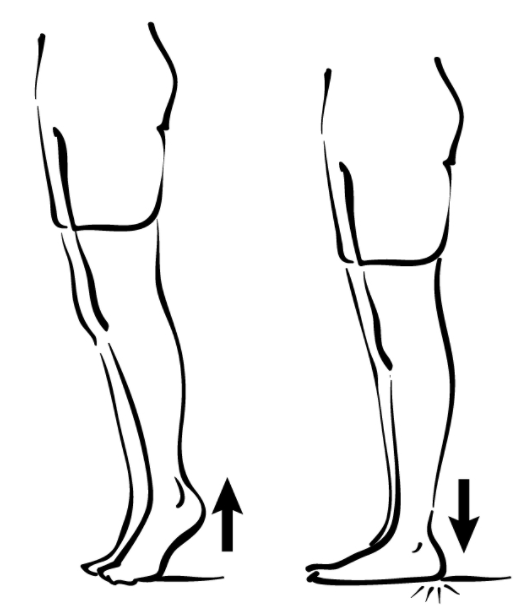

Flat Feet – Not Just A Foot Problem ! | Pediatric Physiotherapy in …

FLAT FOOT- Definition, Symptoms, Causes & Rehabilitation Exercises

What is and How to Fix Flat Feet